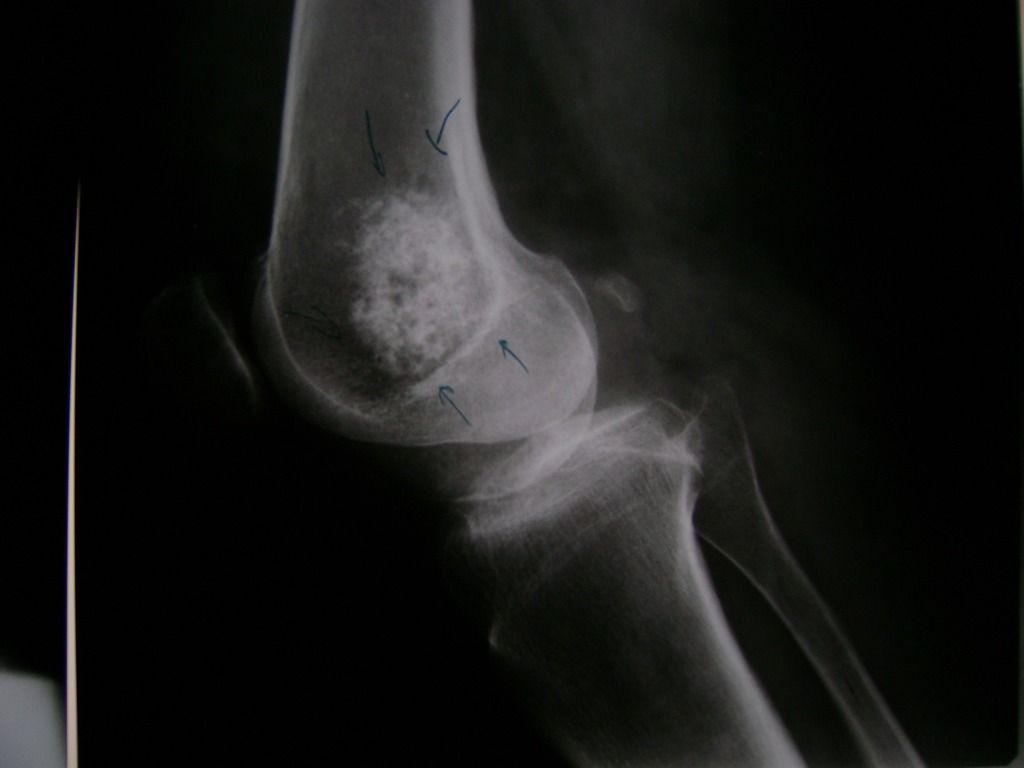

Cirugias en El Salvador - Rodilla

La artroscopia de rodilla es un cirugía en el cual la estructura interna de la articulación es examinada ya sea para realizar un diagnostico o para realizar un tratamiento, este procedimiento se realiza utilizando un instrumento parecido a un pequeño tubo llamado artroscopio.